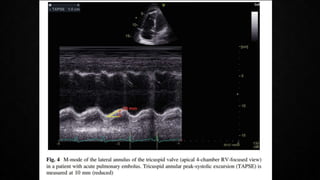

• Decreased tricuspid annular systolic plane excursion (TAPSE) may also be seen in PE

ECHOCARDIOGRAPHY IN PE •Manifestations of RV pressure overload and dysfunction • RV dilatation seen in >25% of patients with PE on TTE and is useful for risk stratification of the disease • 60/60 Sign : combination of a pulmonary ejection acceleration time (measured in the RV outflow tract) of <60ms AND a peak systolic tricuspid valve gradient of <60mmHg • McConnell’s sign : depressed contractility of the RV free wall when compared to the RV apex • Finding present only in 12-20% of unselected PE patients • Decreased tricuspid annular systolic plane excursion (TAPSE) may also be seen in PE • Mobile right heart thrombi (in up to 18% of PE in the ICU) essentially confirm the diagnosis of PE and associated with high mortality rates